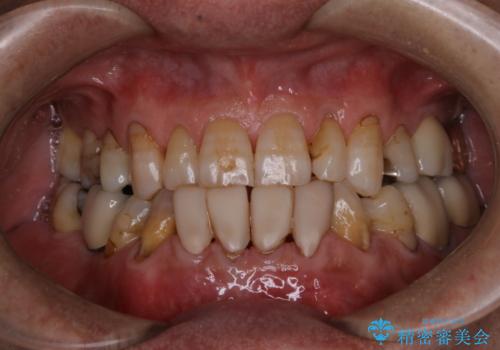

久しぶりのPMTCでメンテナンス

- 忙しくて、しばらくクリーニングをしていないため、全体的にしっかりとクリーニングしてほしいとのことでした。PMTC60分コースを行いました。